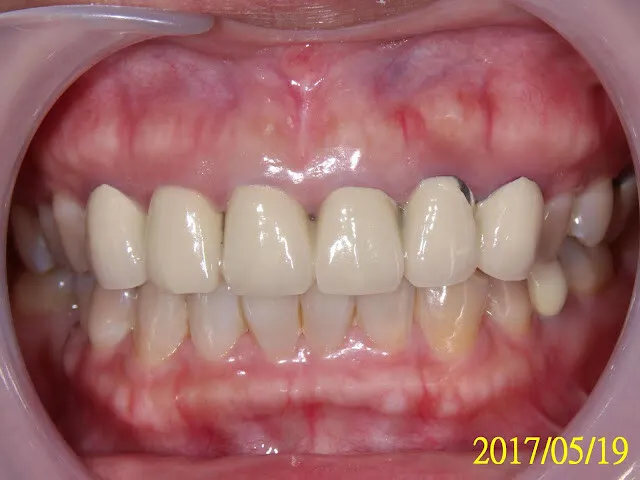

剛好這位臨床案例,算是大工程,我花了很長一段時間才搞定,正好可以說明這些FAQ。

黃小姐在大醫院從事醫療工作為知名醫療人員,有時需上節目,發現前牙區不好看,牙齦發黑、牙齒不美,急於求助於牙醫師希望改善牙齒狀況,以避免損及醫療專業形象。